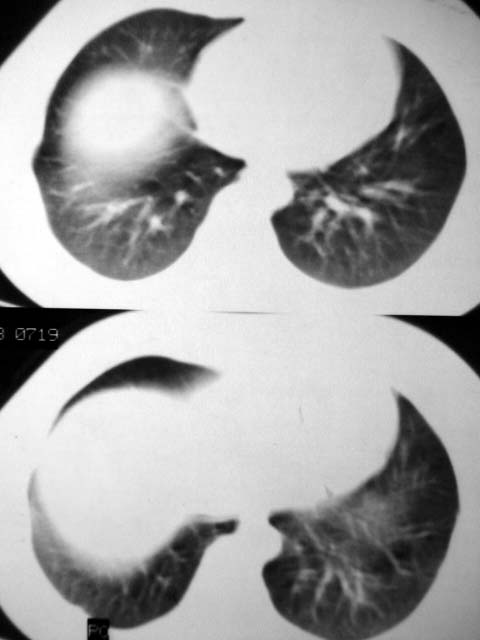

标题: CT12463:女,19岁,炎性假瘤?结核球? [打印本页]

女,19岁,体检时发现。炎性假瘤?结核球?

早产儿,幼时体弱,常感冒肺部感染,13岁后好转。两月前“感冒”后咳嗽两周。

病灶肺纵比较大,边缘平直,周围无卫星灶,考虑炎症。建议抗炎治疗后复查。

病灶片状改变,呈钱币样,周围炎性反应明显,考虑球形肺炎可能性大,球形肺炎与炎性假瘤鉴别的重要一点是,炎性假瘤抗炎治疗不会明显改变。

首先要说ct机太差,片子质量不佳,一定是2秒以上机器的作品!其次ct技师需进一步培训,象这种情况就应该针对病灶部位做薄层或高分辨扫描。不过从上传影像看,患者年轻、病灶周围没卫星灶倒支持炎性假瘤诊断,不过象这种部位也有可能是叶间包裹性积液可能。只是ct机太、太差,很难诊断,如一秒机扫描出来90%可直接诊断,有必要时可结合矢状位三维重建。所以要我说建议患者在亚秒(至少是1秒)机上重扫十分有利于正确诊断。